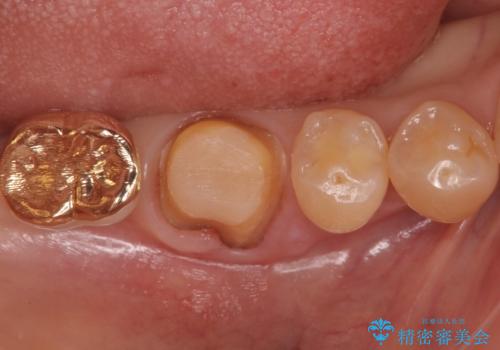

不適合だった詰め物の裏側に大きな虫歯がありました。

セラミックインレーやアンレーでは強度に不安が残るため、クラウンでの修復処置としました。

クラウンでは歯のがたつきを修正することもできます。